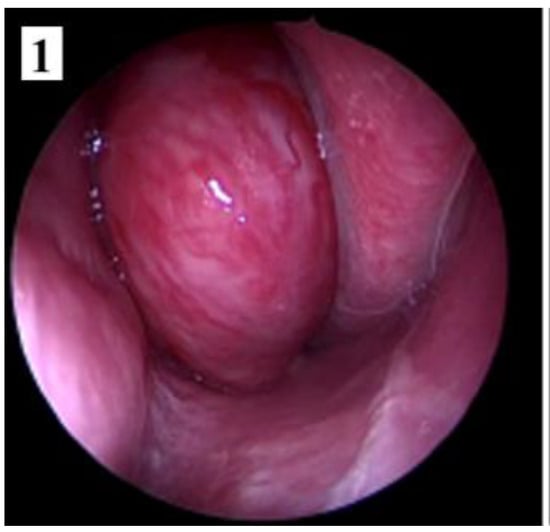

Figure 8.

Preoperative MRI of a stage IIC juvenile angiofibroma. The Holman-Miller sign (the anterior bowing of the posterior maxillary wall) on the CT scan (part 2).